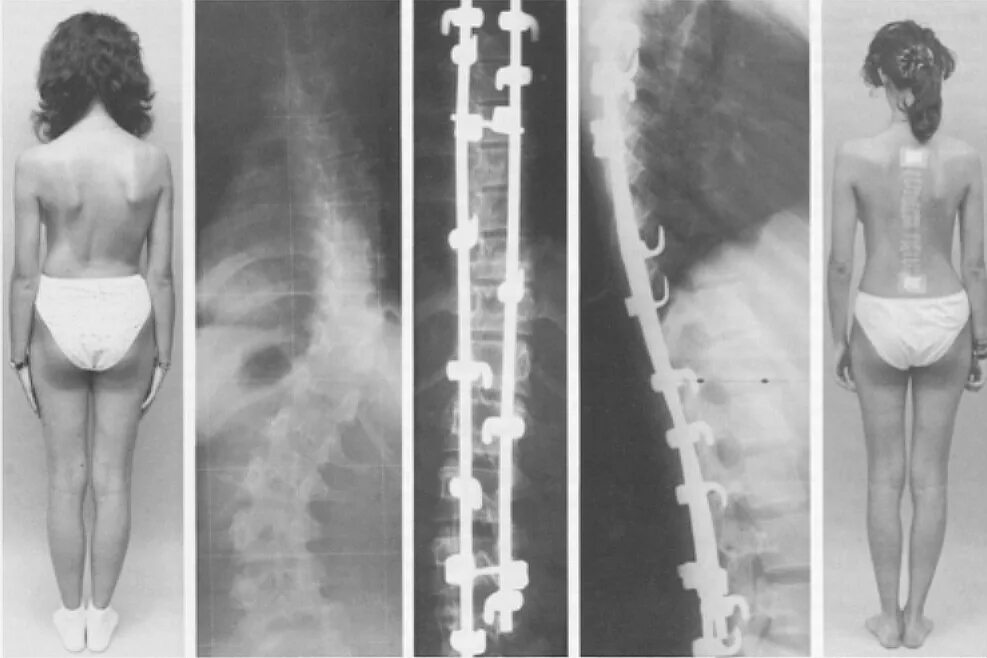

Грудопоясничный сколиоз 3 степени. 3 степени искревле искривление позвоночника. s образный кифосколиоз грудного отдела позвоночника. кифосколиоз грудного отдела позвоночника 2.Сколиоз позвоночника у детей 3 степени. искривление позвоночника у детей сколиоз 3 степени. диспластический сколиоз 2 степени. искривление позвоночника 2 степени у детей.Сколиозе степень искривления позвоночника. искривление позвоночника первой степени.Врождённый сколиоз у ребенка 3 степени. сколиоз позвоночника 3 степени. сколиоз позвоночника 3 степени инвалидность. сколиозе степень искривления позвоночника.Сколиоз позвоночника первая стадия. сколиоз позвоночника 2-3 степени. сколиоз позвоночника 1 степени градусы. 3 стадия сколиоза позвоночника.Грудопоясничный сколиоз 3 степени s образный.Степени сколиоза позвоночника по градусам у детей. 1 степень сколиоза по чаклину рентген. позвоночник при сколиозе 2 степени. сколиоз позвоночника 4 степени рентген.Сколиоз 3 степени лечениеСколиоз позвоночника 3 степени инвалидность. сколиотическая деформация позвоночника 40 градусов. инвалидность сколиоз 2 степени. s образный грудопоясничный сколиоз 2 степени инвалидность.Сколиоз спины 1 степени. сиомиоз позвоночника 1 степени. симптомы сколиоз 1 степени у детей. лечится ли сколиоз 1 степени у подростков.Искривление позвоночника у детей сколиоз 3 степени. рёберный горб сколиоз 2 степени.Сколиоз позвоночника 2 степени. инвалидность сколиоз 2 степени. сколиоз 3 степени инвалидность.Искривление позвоночника 2 степени. дугообразный сколиоз 2 степени. ii степень сколиоза характеризуется. фиксированный сколиоз 2 степени.Сколиоз 3 степени лечениеКорсет шено для шейермана мау. искривление позвоночника шейермана мау. сколиоз болезнь шейермана мау. корсет шено шейерман мао.Сколиоз поясничного отдела 3 степени. сколиоз 3 степени снимок. сколиоз 3 степени рентген после операции. диспластический сколиоз 3 степени.Корсет шено сколиолоджик. корсет функционально-корригирующий шено. корсет шено от сколиоза. корсет шено сколиоз 2 степени.Сколиоз позвоночника 4 степени. грудопоясничный сколиоз 4 степени. кифосколиоз грудного отдела 4 степени. кифосколиоз 2 грудного отдела.Сколиоз 3 степени лечениеСтепени деформации позвоночника при сколиозе. дугообразный сколиоз 1 степени. сколиоз 1 степени грудного отдела и поясничного отдела позвоночника. диагноз сколиоз 1 степени.3 степени искривления осанки. формы сколиоза позвоночника. s образный сколиоз 3 степени. сколиоз позвоночника вид сбоку.Тораколюмбальный сколиоз. ишиалгический сколиоз. сколиоз позвоночника у подростков 14 лет. раймонди сколиоз.Сколиоз 4 степени корсет шено. корсет шено s образный сколиоз. корсет эббота-шено. грудопоясничный сколиоз 3 степени рентген.Операция на сколиоз 2 степени. сколиоз операция рентген. операция на позвоночник сколиоз 2 степени. сколиоз 4 степени рентген.Сколиоз 3 степени лечениеСколиотическая деформация позвоночника. врожденный сколиоз позвоночника. тораколюмбальный сколиоз. правосторонний сколиоз th6-th7.Сколиоз позвоночника 1 степени. левосторонний сколиоз 2й степени. правосторонний сколиоз 1 ст. правосторонний и левосторонний сколиоз.Сколиоз 1 степени сбоку. сколиоз 10 градусов рентген.Корсет шено при сколиозе 4 степени. корсет шено сколиоз 2-3 степени. корсет шено s образный сколиоз.Сколиотическая деформация позвоночника. сколиотическая деформации позвоночника 1-2 степени. кифосколиоз грудного отдела позвоночника.Искривление позвоночника сколиоз. идиопатический сколиоз грудного отдела позвоночника. сколиотическая деформация позвоночника. сколиоз поясничного отдела 3 степени.S образное искривление позвоночника 3 степени. сколиоз поясничного отдела позвоночника по степеням. s образный сколиоз 1 степени по чаклину. сколиоз 2 степени угол искривления.Сколиотическая дуга. дугообразное сколиотическое искривление. сколиоз с 3 дугами искривления. сколиозы 4 степени деформации.Сколиоз 1 степени симптомы. искривление позвоночника 1 степени. этапы сколиоза.Грудопоясничный сколиоз 3 степени s образный. корсет шено s образный сколиоз. сколиоз позвоночника 2 степени.Корсет шено шейерман мау. корсет шено сколиоз 2-3 степени. корсет шено для шейермана мау. сколиоз 3 степени корсет шено.Корсет шено шейерман мао. сколиоз корсет шено. корсет шено кифоз. сколиоз 3 степени корсет шено.Идиопатический правосторонний грудопоясничный сколиоз 2 степени. идиопатический правосторонний грудопоясничный сколиоз 1 степени. идиопатический сколиоз грудного отдела позвоночника. идиопатический грудопоясничный сколиоз 3 степени.Сколиоз корсет шено. сколиоз в подростковом возрасте.Корсет шено кифоз. корсет шено и гимнастика шрот. корсет шено s образный сколиоз. корсет шено при кифозе.Сколиоз 3 степени корсет шено. корсет шено сколиоз 2 степени. корсет шено s образный сколиоз. s образный сколиоз 2 степени грудного отдела.Презентация на тему сколиоз. сообщение на тему сколиоз. сообщение о искривлении позвоночника. сколиоз доклад по биологии.Методики лечения сколиоза. рекомендации врача при сколиозе. сколиоз 1 степени лечится.Сколиоз позвоночника 2-3 степени. сколиоз 2 степени по чаклину. сколиоз позвоночника 1 степени. левосторонний сколиоз 3-4 степени.Градусы искривления позвоночника. 25 градусов искривление позвоночника. сколиоз позвоночника 25 градусов. искривление позвоночника 11 градусов.Сколиоз кифоз грудного отдела. позвоночник сколиоз грудного отдела позвоночника. сколиоз кифоз 3 степени.Искривление позвоночника 3 степени. искривление позвоночника 2 степени.Нейрофиброматоз сколиоз. миопатический сколиоз. клиника сколиоза позвоночника.Сколиоз корсет шено. сколиоз 3 степени корсет шено. корсет шено сколиоз 2-3 степени. сколиоз 4 степени корсет шено.Операция харрингтона сколиоз. метод харрингтона сколиоз рентген. дистрактор харрингтона. сколиоз 4 степени рентген.Кифосколиоз грудного отдела позвоночника 1. правосторонний и левосторонний сколиоз. идиопатический сколиоз грудного отдела позвоночника. кифосколиоз пояснично крестцового отдела.Идиопатический грудопоясничный сколиоз. идиопатический грудопоясничный сколиоз 1 степени. юношеский сколиоз 2-3 степени.Сколиоз 3 степени корсет шено. шено при сколиозе 4 степени. корсет шено сколиоз 2-3 степени. сколиоз 4 степени корсет шено.Сколиоз боковое искривление позвоночника. идиопатический сколиоз 3 степени. диспластический кифосколиоз. идиопатический s-образный сколиоз 4 степени..Сколиоз 3 степени операция. сколиоз 4 степени рентген операция. операция на позвоночник сколиоз 3 степени. операция харрингтона сколиоз.Паралитический сколиоз. сколиоз кифоз 3 степени. миопатический сколиоз. кифоз позвоночника 4 степени.Сколиоз 3 степени лечениеСколиоз позвоночника горб. рёберный горб сколиоз 2 степени. рёберный горб сколиоз 3-4 степени. сколиоз позвоночника схема.Сколиоз грудного отдела позвоночника. боковое искривление позвоночника. сколиоз позвоночника 2 степени.Кифосколиоз грудного отдела позвоночника. сколиотическая деформация позвоночника. сколиоз позвоночника сколиоз.Корсет шено кифоз. корсет шено для позвоночника кифоз. корсет шено сколиоз 2 степени. корсеты шато при сколеозе.Статистический сколиоз. упражнения для s образного сколиоза 3 степени. стабильность позвоночника.Сколиоз позвоночника правосторонний 2 степени. s образный сколиоз грудного и поясничного отдела 2 степени. левосторонний грудопоясничный сколиоз. левосторонний s образный сколиозе 2 степени.Сколиоз 1-2 степени. сколиоз 2 степени презентация. паралитический сколиоз.Сколиоз 2 степени искривление 17 градусов. фиксированный сколиоз 2 степени при угле искривления 17 градусов. сколиоз отклонение 1 степень. угол искривления при сколиозе 2 степени.Сколиоз 3 степени лечениеСколиоз 3 степени лечениеСколиоз позвоночника влево. отклонение оси позвоночника вправо в грудном отделе. сколиоз отклонение 1 степень. сколиоз позвоночника первая стадия.Дистрактор харрингтона. сколиоз 4 степени рентген. операция на позвоночнике сколиоз 4 степени. сколиоз позвоночника 4 степени рентген.Анталгический сколиоз. левосторонний грудопоясничный сколиоз. сколиоз грудного отдела позвоночника 2 степени. s образный сколиоз грудного отдела позвоночника.Корсет эббота-шено. корсет шино шино. дикуль корсет шено. сколиоз 3 степени корсет шено.Сколиоз описание. z образный сколиоз. сколиотическая болезнь позвоночника.Грудопоясничный сколиоз 3 степени s образный. сколиоз позвоночника у взрослых 3 степени. s образный грудопоясничный сколиоз 2 степени. s образный сколиоз 2 степени поясничного отдела.Идиопатический s образный сколиоз. с образный сколиоз 4 степени. s образное искривление позвоночника. сколиоз 2 степени s образный идиопатический.